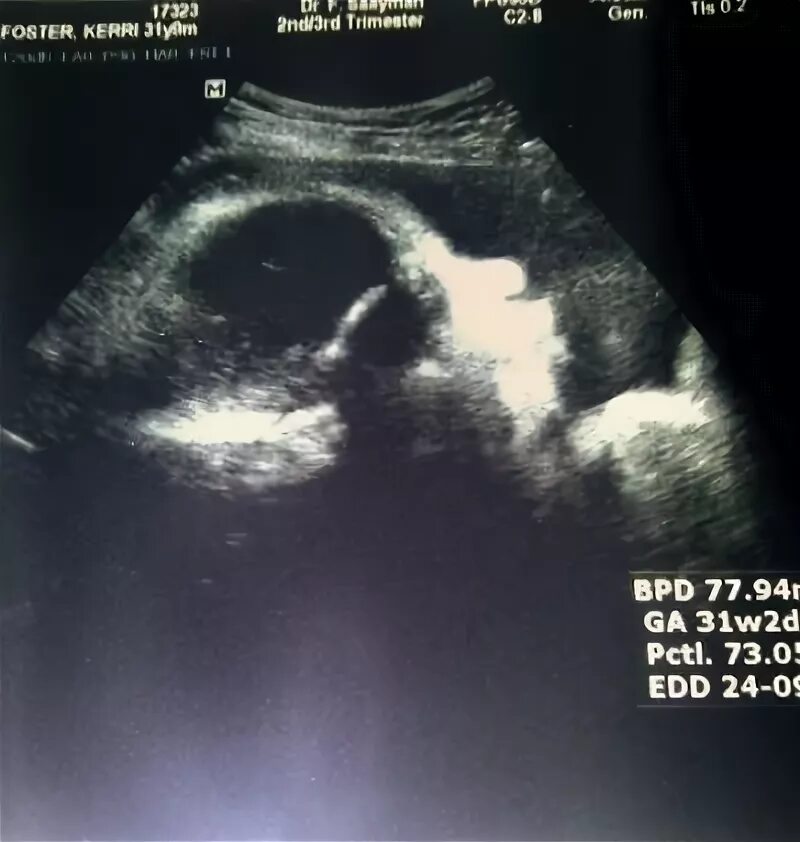

Форум беременных 30 недель